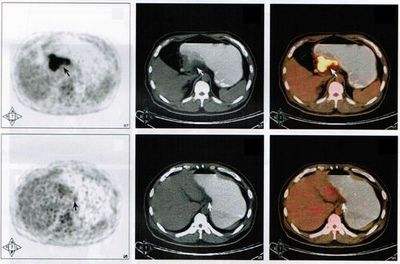

PET全称为正电子发射计算机断层显像(positron emission tomography PET),是反映病变的基因、分子、代谢及功能状态的显像设备。它是利用正电子核素标记葡萄糖等人体代谢物作为显像剂,通过病灶对显像剂的摄取来反映其代谢变化,从而为临床提供疾病的生物代谢信息。是当今生命科学、医学影像技术发展的新里程碑。

PET/CT:将PET和CT有机的结合在一起,使用同一个检查床合用一个图像工作站,PET/CT同时具有PET,CT及将PET图像与CT图像融合等功能。

PET看的是组织的代谢。也就是说,通过异常的代谢来判断全身上下是否有病变,其中最敏感的要属肿瘤性病变,因为肿瘤的特点就是代谢旺盛。但是PET也存在相当的局限性,首先就是扫描层面的问题,扫描整个人,层面相对比单独扫一个器官要粗略很多,一些细小的问题可能被忽略。然而很多良性疾病,代谢改变不大,在PET扫描的时候也不会被发现。

另外,即使看到病灶,由于扫描的精确度问题,也仅仅可以定位病灶的存在,对于其具体性质还需要进行进一步的专项扫描。在发达国家,PET广泛应用于临床,已成为肿瘤、冠心病和脑部疾病这三大威胁人类生命疾病诊断和指导治疗的最有效手段。

pet-ct检测界面